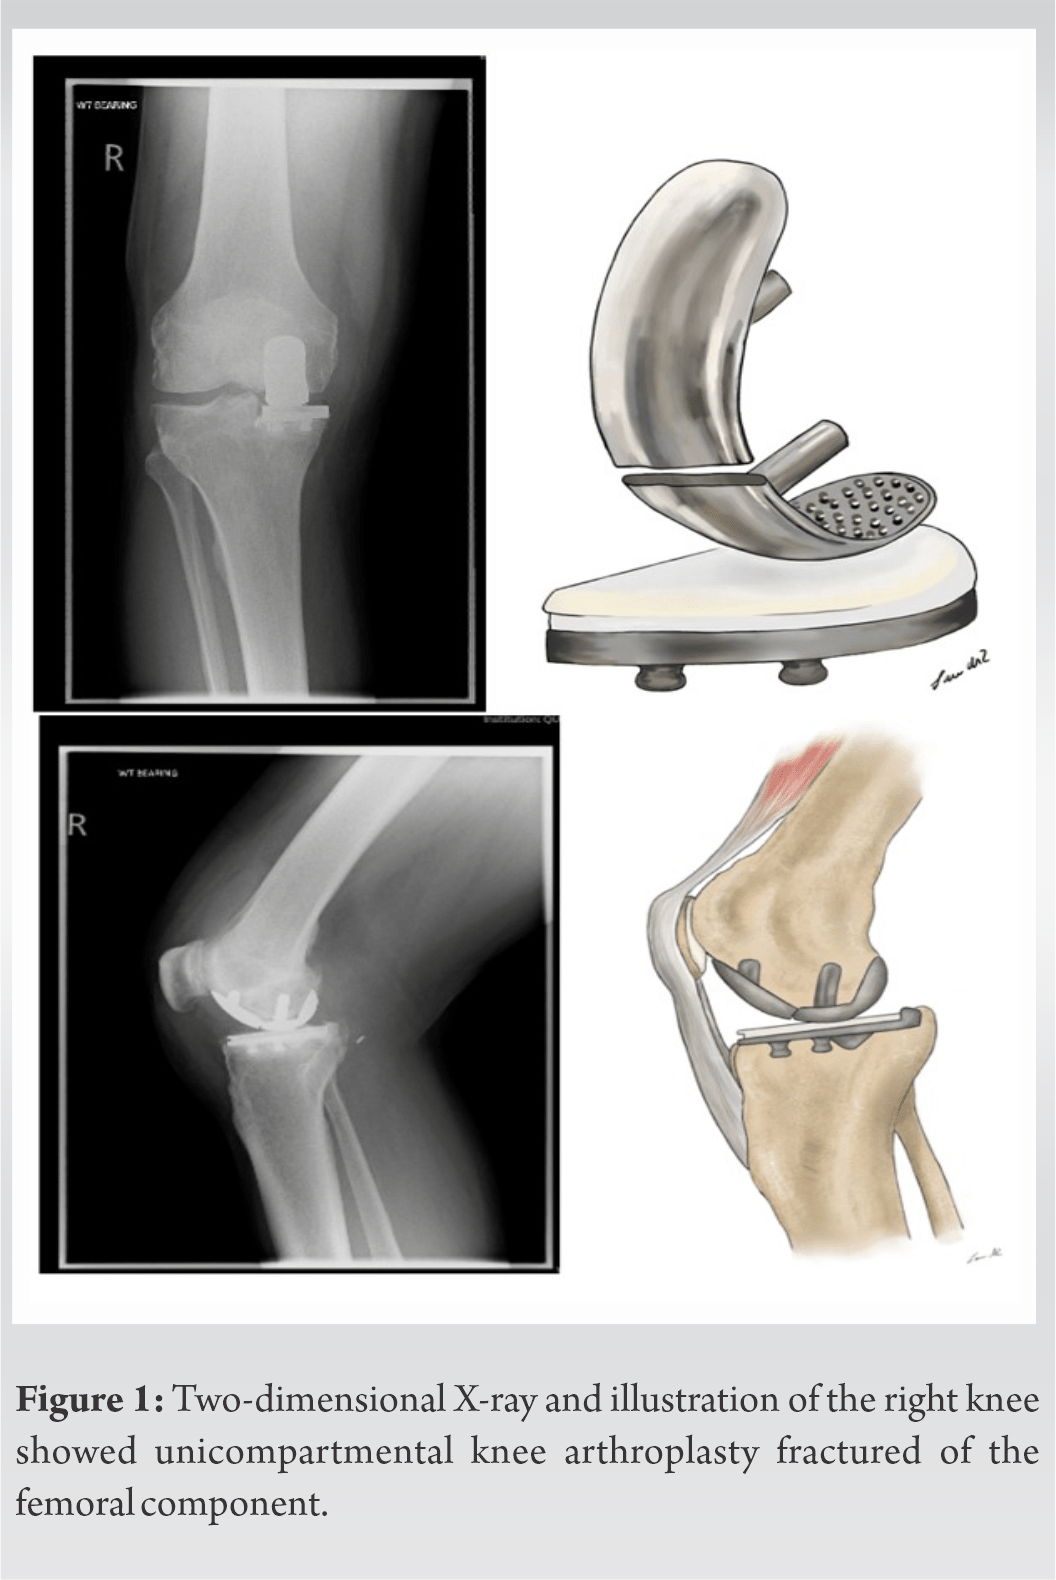

From jocr.co.in

A Case Report of Knee Arthroplasty Fracture of the Cpt For Unicompartmental Knee Arthroplasty Learn about the indications, technique, complications and outcomes of unicompartmental knee arthroplasty, a surgical option for knee arthritis in one. See all arthroplasty knee cpt codes. Find out if you are a candidate, what to expect before and after. Learn about unicompartmental knee replacement, a surgery that resurfaces only one area of the knee affected by osteoarthritis. Discussions on how. Cpt For Unicompartmental Knee Arthroplasty.